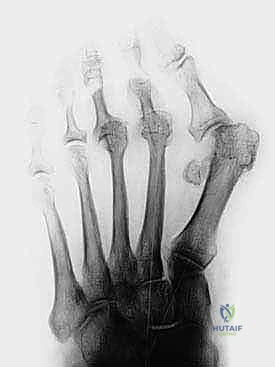

2. التصوير بالأشعة السينية (X-rays) مع تحمل الوزن

يجب أخذ صور الأشعة بينما يكون المريض واقفاً (Weight-bearing). هذا يسمح للدكتور هطيف بتقييم الطول النسبي لعظام مشط القدم، زوايا المفاصل، ودرجة الخلع الفعلي تحت تأثير وزن الجسم.